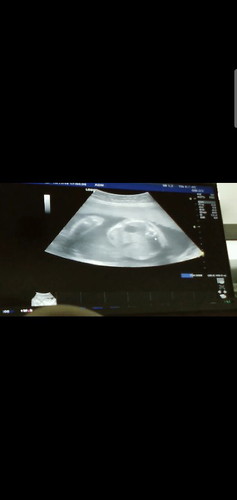

ท้อง6เดือน เด้กกับหัวแล้ว

ตอนนี้25วิค 2วัน ไปหาหมอมาวันนี้ หมอบอกเด็กกลับหัวแล้ว แต่เด็กแข็งแรงดี น้ำหนักเกินเกณฑ์ ปกติต้อง 700 นี้ 923 นัดคลอด26 กพ เสี่ยงคลอดก่อนกำหนดไหมจ้ะแม่ๆๆ แล้วฉันตรายไหม